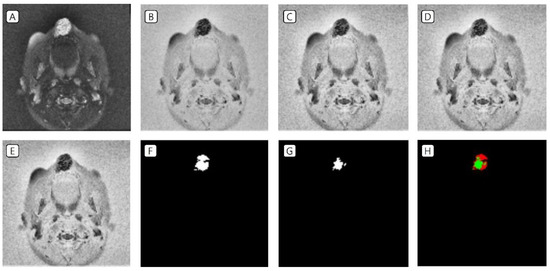

3.1. Cases: Data of the Training Set

3.2. Cases: Data of the Test Set